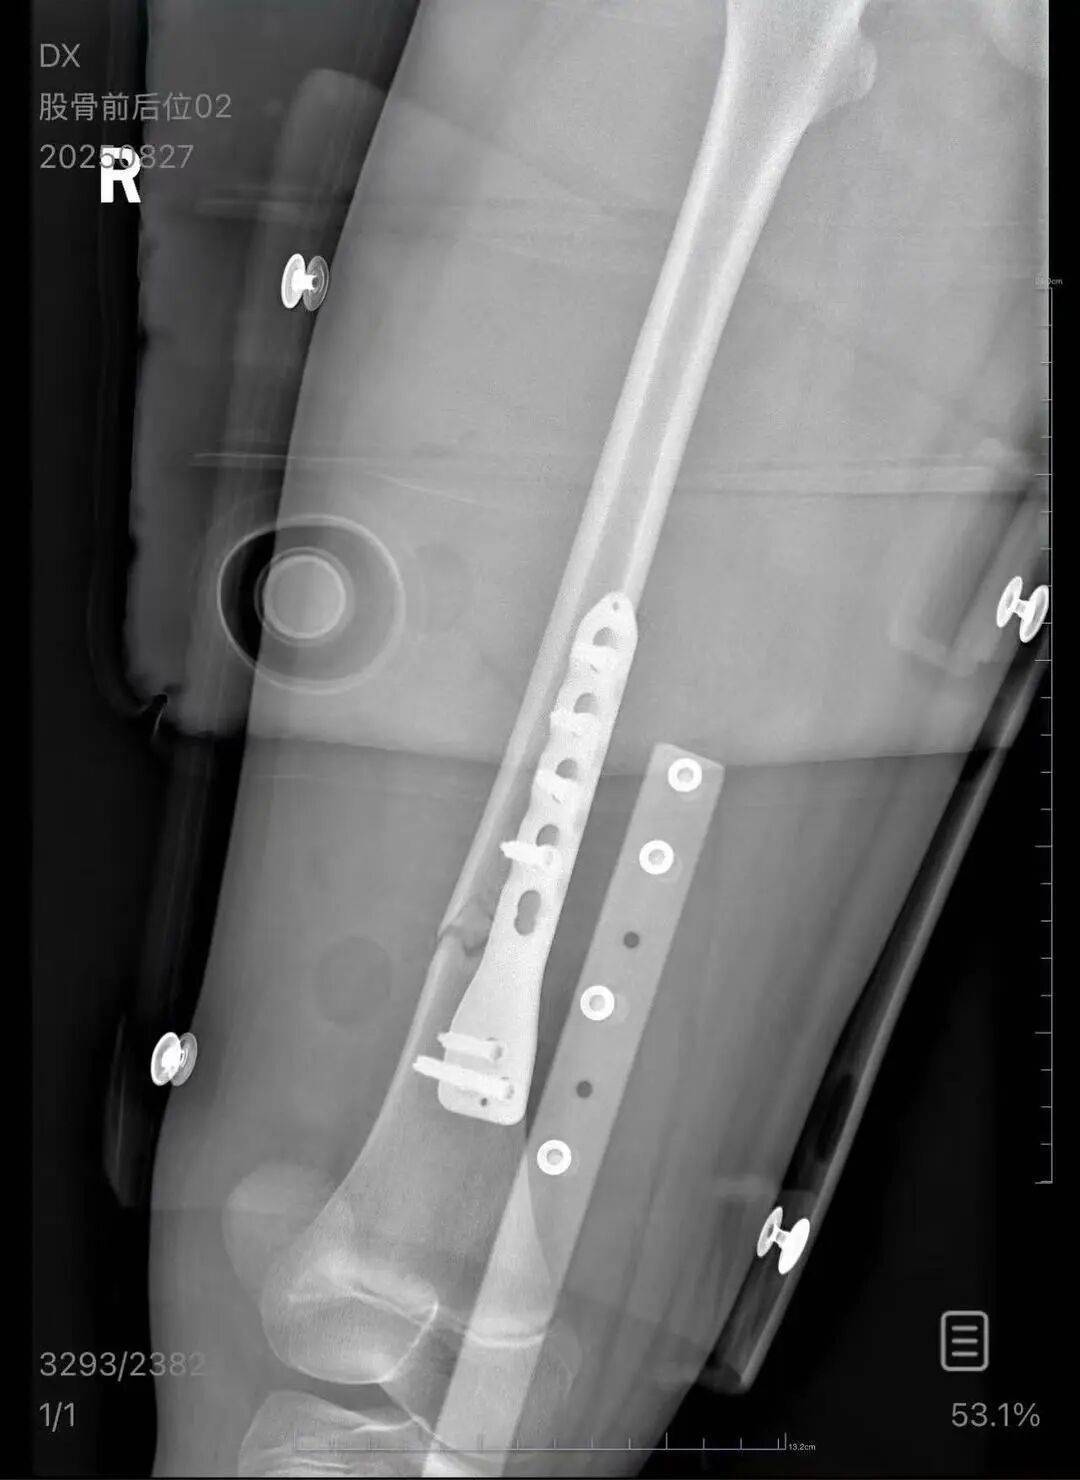

▲朱女士女儿手术后拍的X光片 受访者供图

朱女士向记者出示的医院病历显示,8月24日凌晨,朱女士的女儿到医院就诊理邦仪器股票。医院诊断朱女士的女儿右股骨骨折,需要住院进一步治疗。